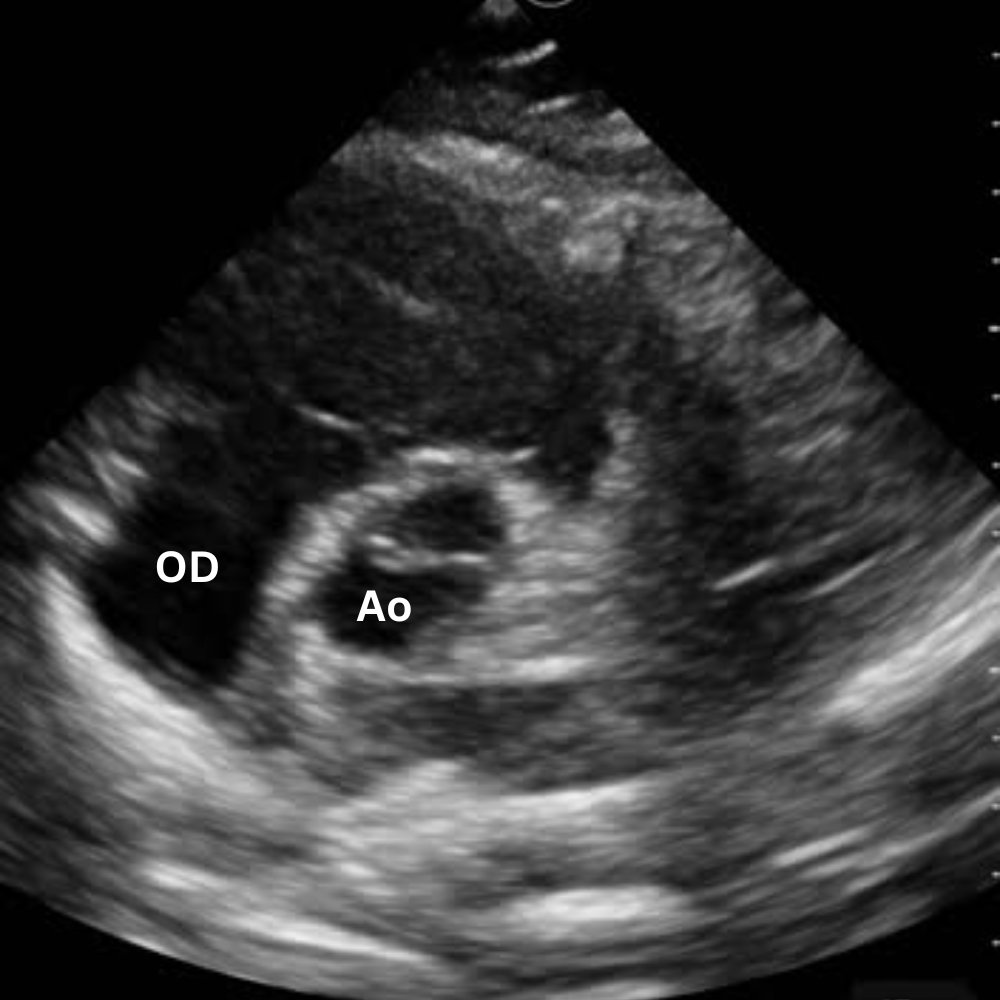

🔹 Vue Apicale Quatre Cavités

→ Quelle cavité domine ?

Placer la sonde près de l’apex (5e espace, région du mamelon gauche), marqueur vers l’épaule gauche. Glisse légèrement jusqu’à un bon espace intercostal, puis bascule la sonde vers la base du cœur jusqu’à voir VG, VD, OG et OD dans le même plan.

On visualise les quatre cavités, les valves mitrale et tricuspide et le septum.

Permet de comparer VD et VG (surcharge droite si VD ≥ VG), d’apprécier la cinétique globale et de repérer un épanchement péricardique circonférentiel.